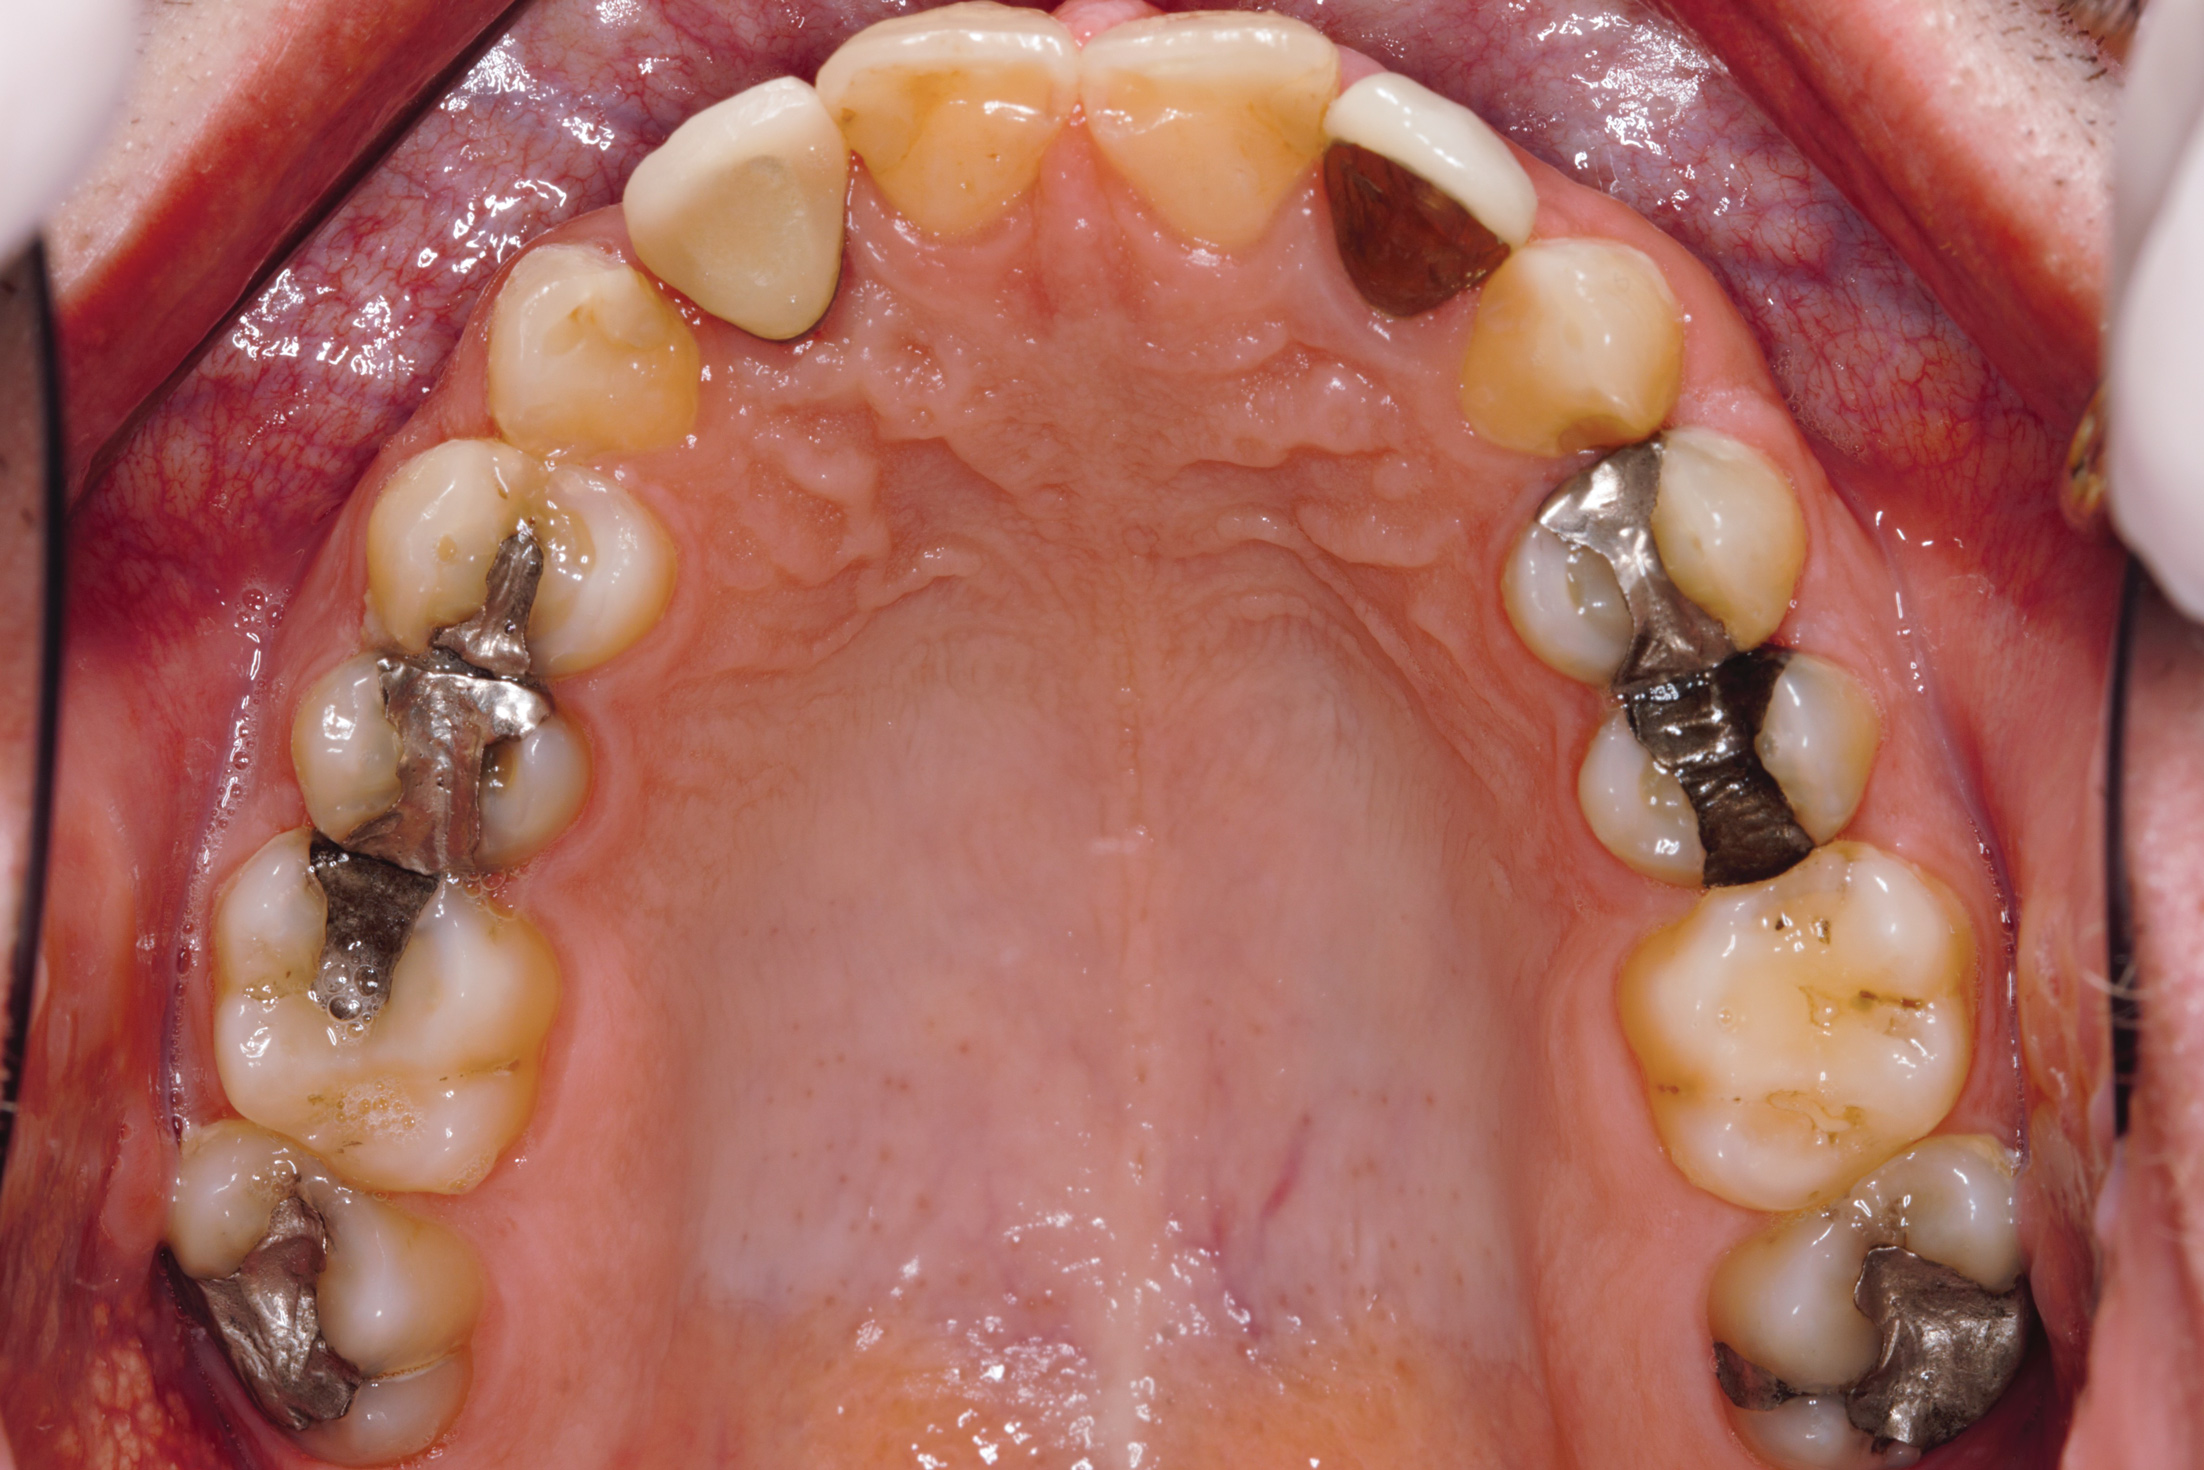

Fig 3. Maxillary occlusal view of worn dentition through erosion.

Figure 3

Fig 13. Prosthetic phase completion. Maxillary occlusal view. Note arch form change without compromise to the buccal alveolar bone and periodontal phenotype.

Figure 13